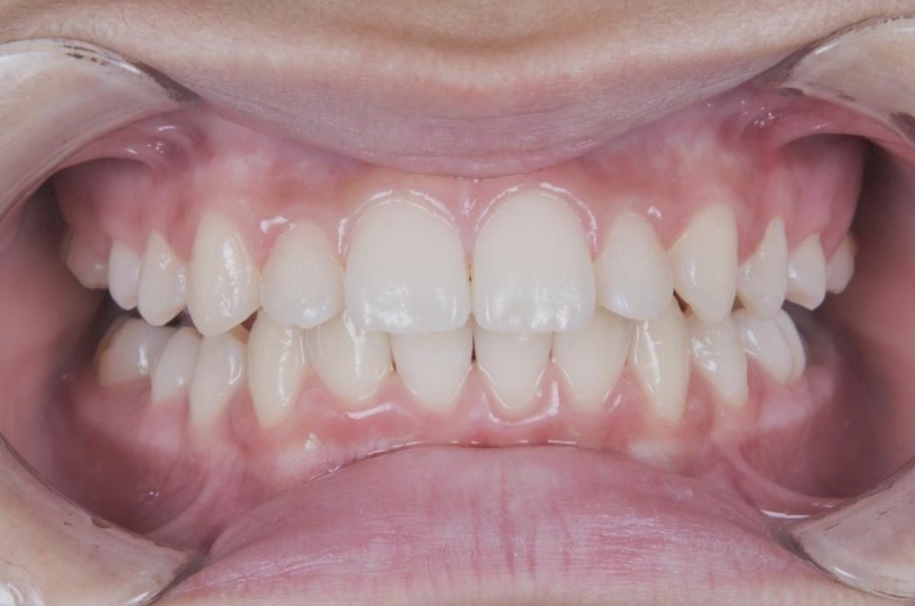

1年3ヶ月の治療で、きれいな歯並びへと改善しました。

After 1

After 3